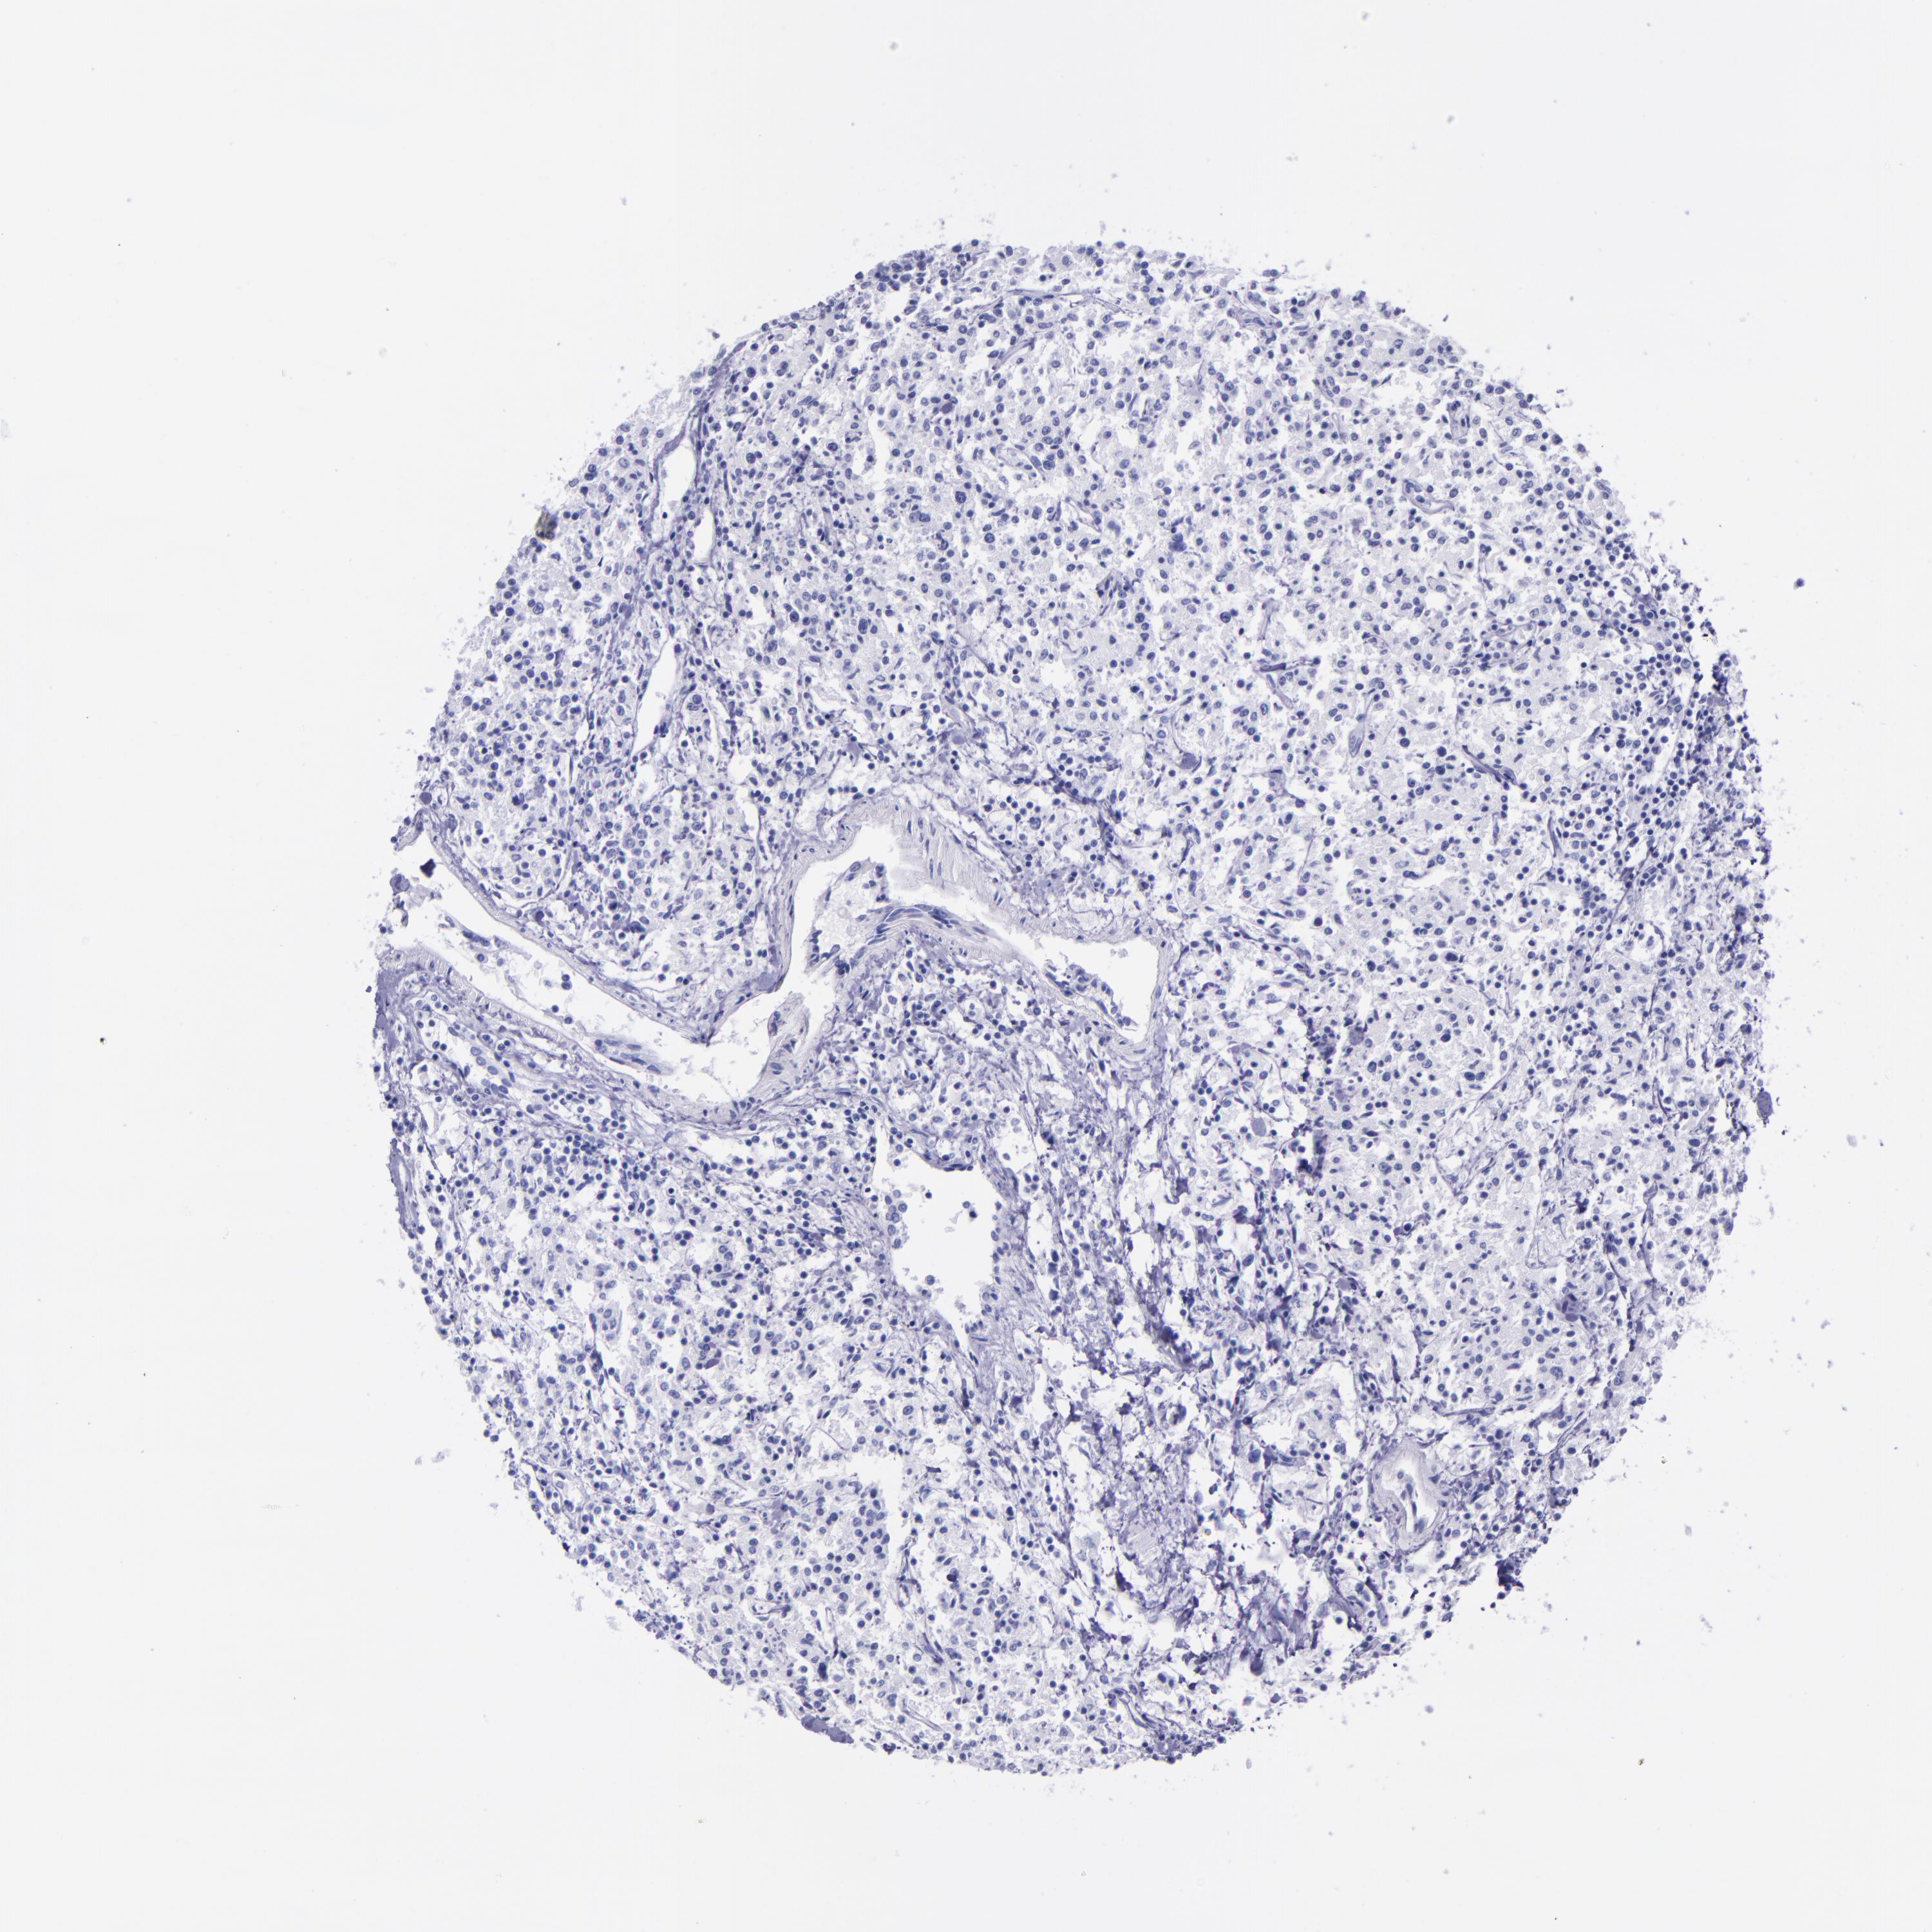

CANCER LYMPHOMA Show tissue menu

LYMPHOMA - Protein expressioni

A mouse-over function shows sample information and annotation data. Click on an image to view it in a full screen mode. Samples can be filtered based on level of antibody staining by selecting one or several of the following categories: high, medium, low and not detected. The assay and annotation is described here.

Each image is clickable and will lead to virtual microscopy that enables deeper exploration of all samples and also displays staining intensity scores, fraction scores and subcellular localization as well as patient and tissue information for each sample.

Antibody HPA049222

Hodgkin's disease, NOS

Malignant lymphoma, non-Hodgkin's type, High grade

Malignant lymphoma, non-Hodgkin's type, Low grade